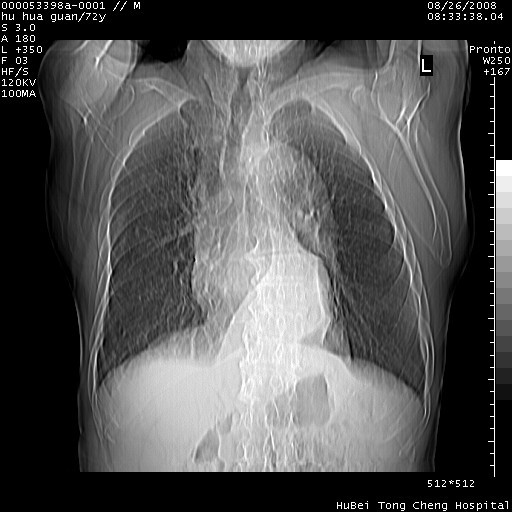

图像及窗宽窗位均不理想。周围性肺癌/胸腔积液/纵隔积液。

1、右肺周围性肺癌、胸腔积液(双)

2、建议食道吞钡和增强检查排除食道和主动脉病变

3、后纵隔淋巴类肿瘤